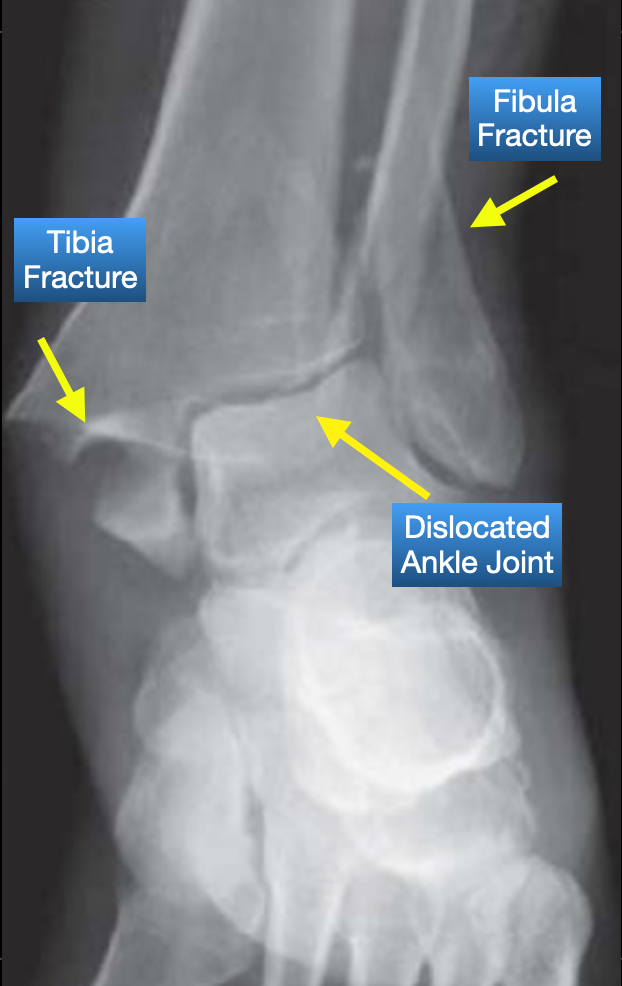

The ankle is a complex area that is made up of multiple joints between different bones that each allow specific motions. The talus is a bone in the middle of the ankle, and the long bones of the lower leg (tibia and fibula) form an arch around the dome-shaped top of the talus. Most of your body weight is carried through the tibia to the talus. It takes a lot of force, typically through an impact from the side on a planted leg to cause an ankle dislocation. Ankle dislocations are usually paired with fractures to the lowest parts of the tibia and fibula, and possibly even the domed top of the talus from where the bones hit each other as the talus leaves its position in the centre of the arch. Beyond the fractured bones, ankle dislocations are also devastating to the soft tissues in the ankle. The ligaments that attach the bones together to provide stability get torn or severely stretched causing gross instability. There may also be injury to the tendons that cross the ankle to attach the lower leg muscles to the foot, or damage to the blood vessels or nerves that supply the foot. The extensive damage with ankle dislocations means that surgery is the most common treatment option. Plates and screws are used to secure the fracture sites, and the procedure may include reconstructing or repairing damaged soft tissues to restore stability. After surgery, patients are non-weight bearing for a time and then gradually ease back into weight bearing, range of motion and progressively increasing strengthening. This injury is definitely season ending for Warner, however not necessarily career ending.